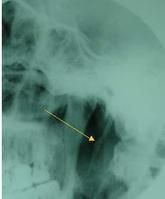

茎突综合征[1],又称茎突过长症,以往认为是一罕见病。茎突综合征是因茎突过长或其方位、形态异常刺激邻近血 管神经而引起的咽部异物感、咽痛或反射性耳痛、头颈部痛和涎腺增多等症状的总称。常见于成年人。起病缓慢,病史长短不一,常有扁桃体区、舌根区疼痛,常为单侧,多不剧烈,可放射到耳部或颈部,吞咽时加重。咽异物感或梗阻感较为常见,多为一侧,吞咽时更为明显,有时在讲话、转头或夜间加重。也可引起咳嗽、当颈动脉受到压迫或磨擦时,疼痛可从一侧下颌角向上放射到头颈部或面部。有时可有耳鸣、流涎、失眠等神经衰弱的表现。